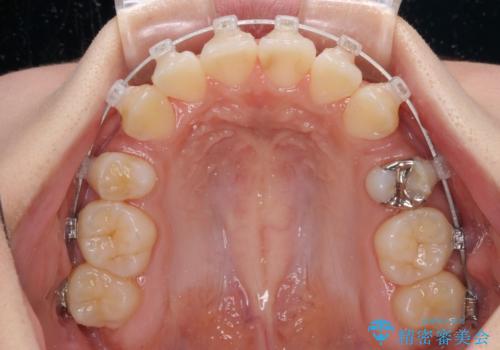

- 矯正装置

- クリアブラケット

- 前歯の叢生と八重歯を気にして来院された患者様です。

叢生が強く、奥歯の咬合も左右差が大きかったため、上下左右4本を抜歯して、ワイヤー矯正を行うこととしました。

20歳前後と年齢が若かったため、非常にスムーズに歯列が整い、1年半をかけずに治療を終えることができました。